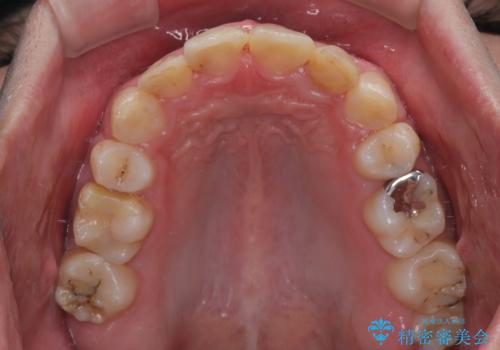

- 口元の突出感と奥歯の咬み合わせの悪さを気にして来院された患者様です。

口元はやや突出感があったため、上下左右の第一小臼歯4本を抜歯してワイヤー矯正にて抜歯矯正を行うこととしました。

また、左右ともに最後臼歯が交叉咬合になっており、外側に飛び出している上顎の最後臼歯を補助装置を利用して、積極的に内側に引き込むようにしました。